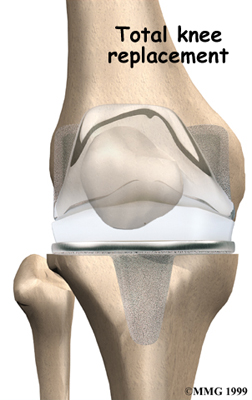

Artificial Knee Replacement

An artificial knee replacement is the ultimate solution for advanced knee OA.

Surgeons prefer not to put a new knee joint in patients younger than 60. This is because younger patients are generally more active and might put too much stress on the joint, causing it to loosen or even crack. A revision surgery to replace a damaged prosthesis is harder to do, has more possible complications, and is usually less successful than a first-time joint replacement surgery.

Related Document: FYZICAL Wilmington's Guide to Artificial Joint Replacement of the Knee